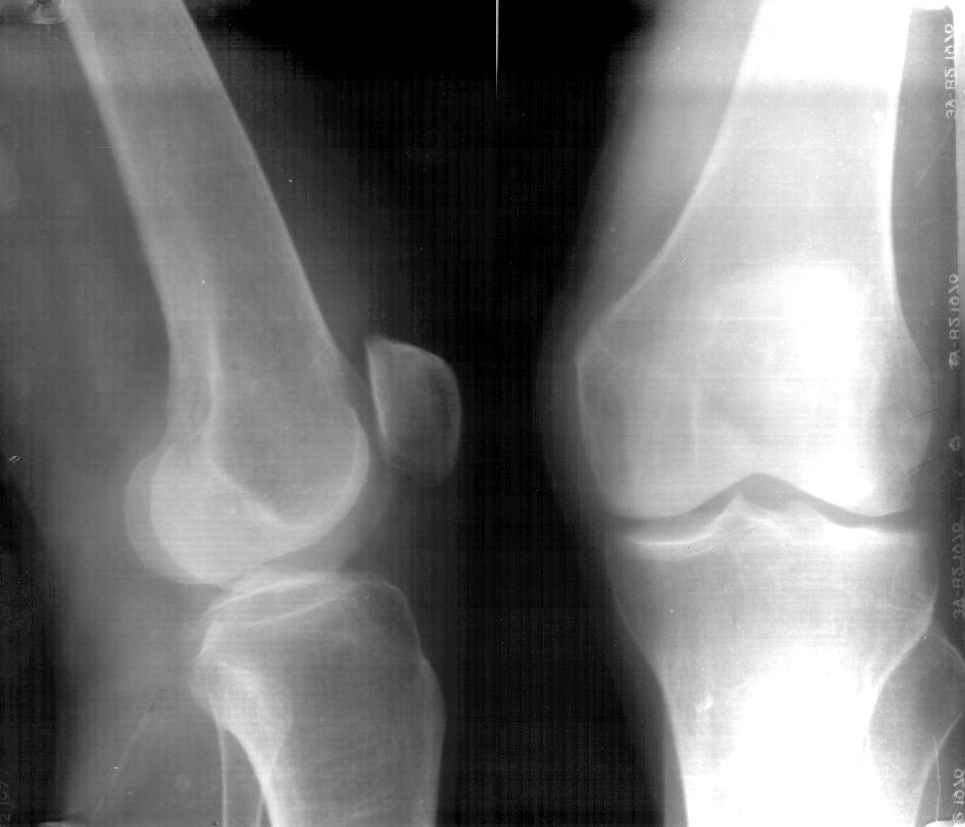

Больная К.85 лет, получила незначительную травму в конце июля 2002 года (рентгенограммы от 26.07.2002). Ушиб коленного сустава, отека не было, гемартроза не было. Лечилась местными средствами, троксевазиновая мазь, водочные компрессы. В дальнейшем развился посттравматический периартрит правого коленного сустава, синовиит правого коленного сустава. Больная на дом приглашала много различных врачей, из санаторной сети, частных хирургов, из скудных полученных данных возможно было выяснить, что получала диклофенак-натрий внутримышечно, примерно 10 раз. Несколько внутрисуставных инъекций, сколько и с каким промежутком выяснить не удалось, но более менее достоверно, что один раз вводили гидрокортизон и один раз кеналог-40. Записи практически никто не оставлял.На данный момент больная категорически отказывается от госпитализации в любое из предложенных отделений ни только для лечения, но и для обследования. Ищет врача, который назначит "правильную" мазь.Моя версия, асептический некроз наружного мыщелка правого бедра, после многократного введения гормональных противовоспалительных препаратов (рентгенограммы от 07.05.03).

AB> Моя версия, ассептический некроз наружного мыщелка правого бедра,

Многократного введения вроде и не было? Вообще, хрящевые язвы после десятков инъекций кеналога вполне ожидаемы, но тут такой остеолиз... На онкологию тоже не очень похоже... И на артрит не очень...

В возрасте 84 лет незначительная травма на фоне остеопороза могла послужить причиной перелома ( что возиожно и присутствует на предоставленных RTG

особо похоже на боковых), на этом фоне в результате блокад, пусть и не многочисленных, развился асептический некроз мыщелка бедра.

D-z:Старый несросшийся перелом наружного мыщелка правого бедра.Посттравматический ( ятрогенный?)

асептический некроз наружного мыщелка бедра.

Если верить клинике (отсутствие гемартроза) говорить о первичном переломе наружного мыщелка бедра нельзя. Да и не ходила бы больная с таким переломом. Плюс ко всему, практически, не бывает при данной локализации переломов без смещения.

Моё мнение: Асептический некроз наружного мыщелка бедра с патологическим переломом и рассасыванием приферического фрагмента.

Картина близкая к асептическому некрозу головки бедра при медиальном перломе шейки бедра - но в этом случае перелом первичен, а некроз вторичен.

Еслии верить многократному применению гормональных препаротов, то первичный (без травмы) асептичесий некроз имеет право быть. Даже не столько асептический некроз, сколько остеопоротическая резорбция костной ткани медикаментозного происхождения.